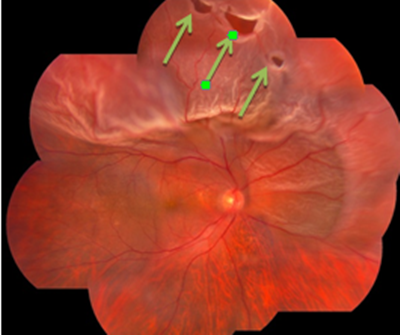

高度近视眼由于眼轴不断拉长,过长的眼球常常造成视网膜、脉络膜之间的循环障碍,供血不足,导致色素细胞的变性、萎缩。除眼底后极部形成片状萎缩斑外,周边部视网膜也常常发生变薄改变,变性区的视网膜非常薄,非常容易形成裂孔。再加上玻璃体液化、以及牵拉视网膜,液化的玻璃体易通过裂孔进入视网膜神经上皮层与色素上皮层之间积存,从而引起视网膜脱落。

视网膜脱落如果不重视,当脱落至黄斑位置时,将会有失明风险,就算后期进行手术,术后预后情况也不佳。

(视网膜脱落)

当发生视网膜脱落后,部分患者没有明显自觉症状,而有些患者眼前的会出现大量飞蚊,并伴随闪光及视野缺损的情况。